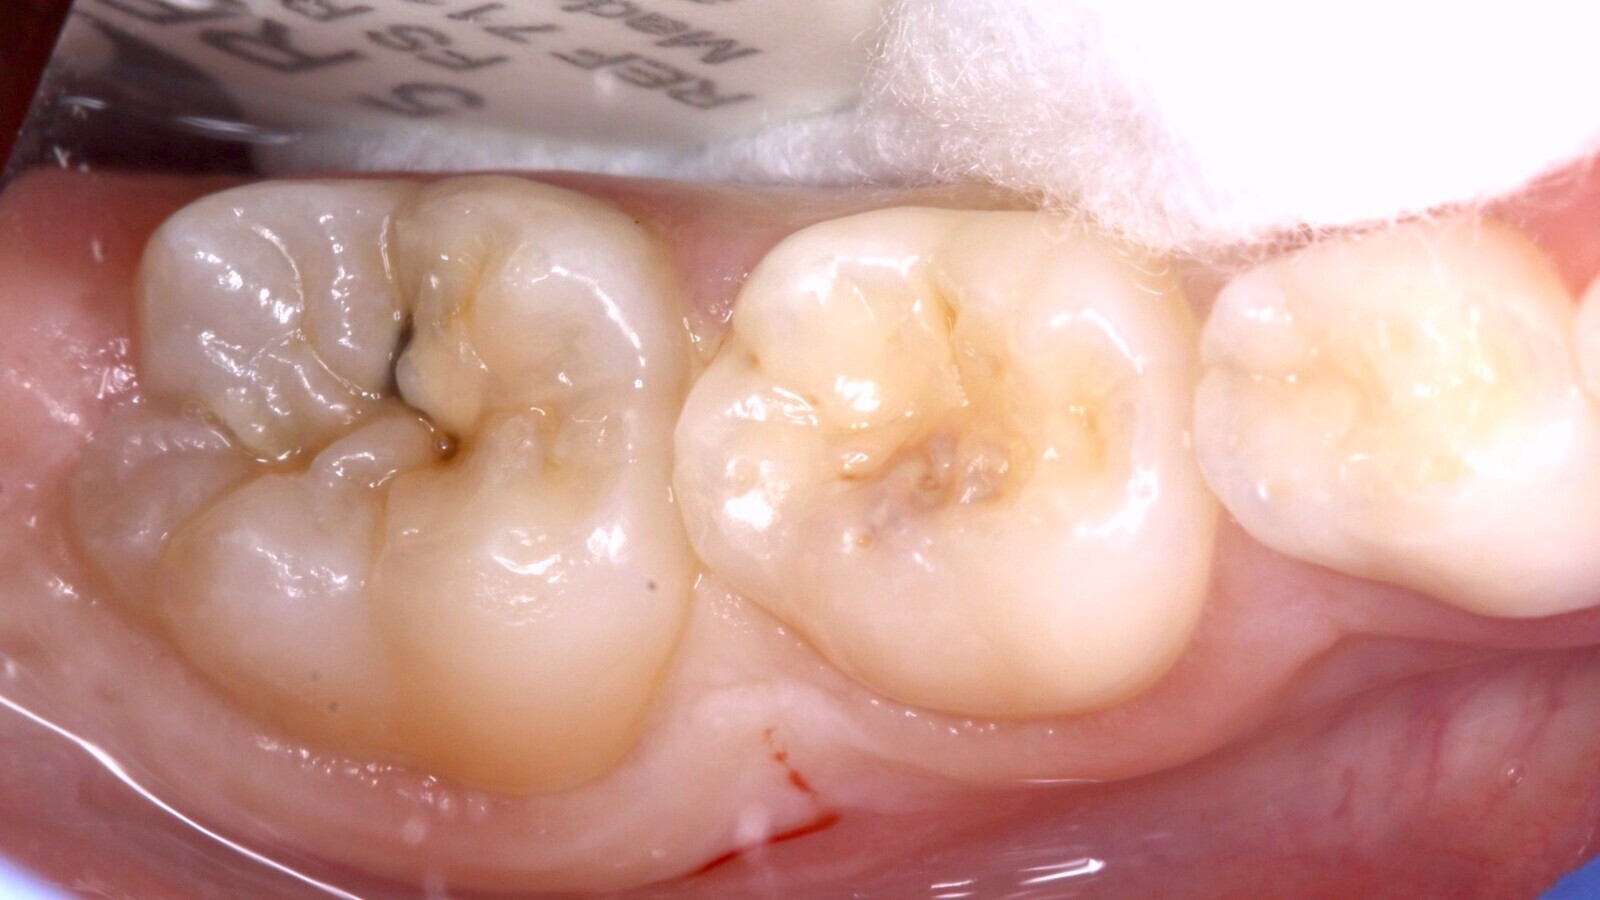

Imágenes inicial (A), radiográfica (B) y final (C) del diente 46 de una paciente de 7 años con sensibilidad dentinaria, que se restauró utilizando el material estético de fraguado rápido EQUIA Forte fil, y la resina compuesta everX Flow. Estos materiales utilizan la nueva tecnología de vidrio híbrido y actúan de forma sinérgica para formar un material más fuerte de colocación en bloque.

Fig. 1. El diente 46 presenta una sombra subyacente en la dentina apreciada desde oclusal.

Al realizar el examen clínico, el diente 46 presenta una sombra subyacente en la dentina apreciada desde oclusal (Fig. 1), que al manejar el sistema internacional de detección y valoración de caries dental se considera una lesión ICDAS 4 (sombra subyacente en la dentina con esmalte aparentemente intacto). El examen radiográfico, con una exposición de aleta de mordida, evidencia una imagen radiolúcida que alcanza al tercio medio de la dentina (Fig. 2).